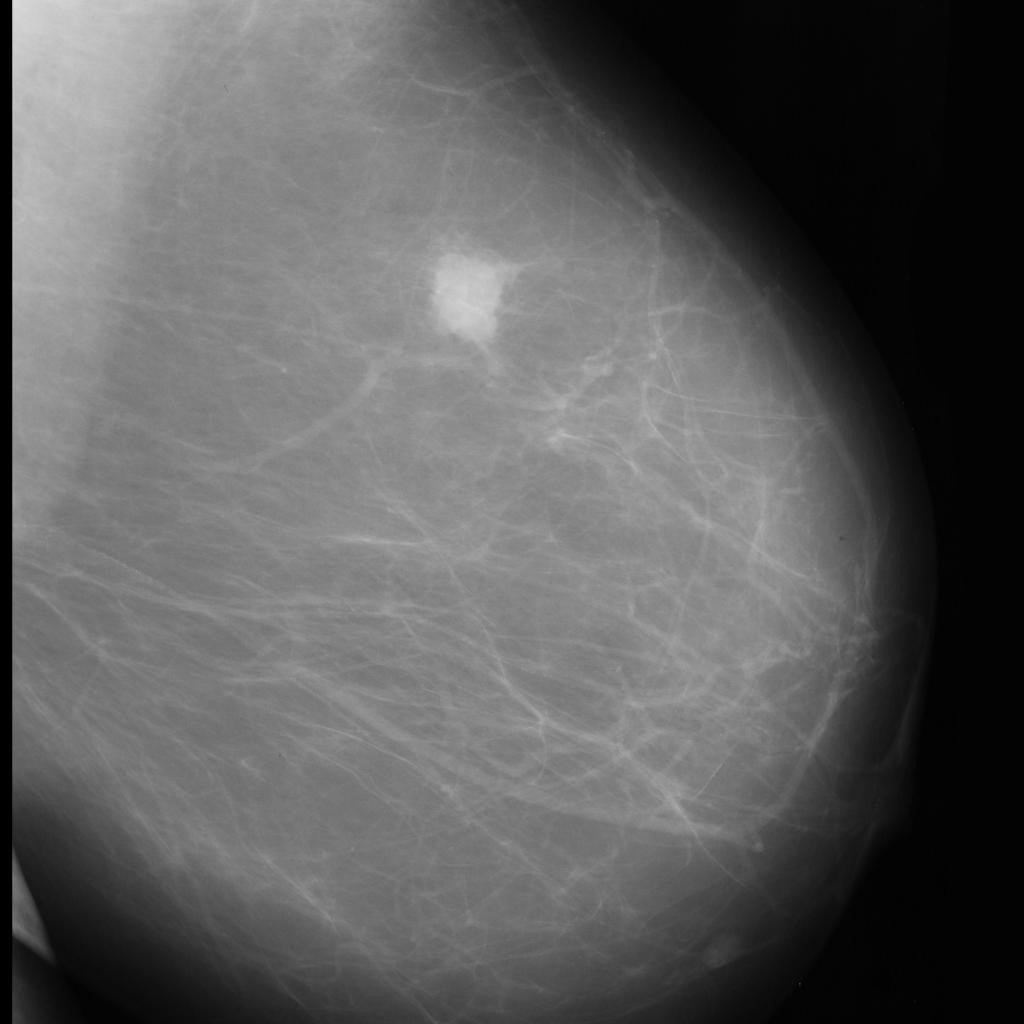

benign

malignant